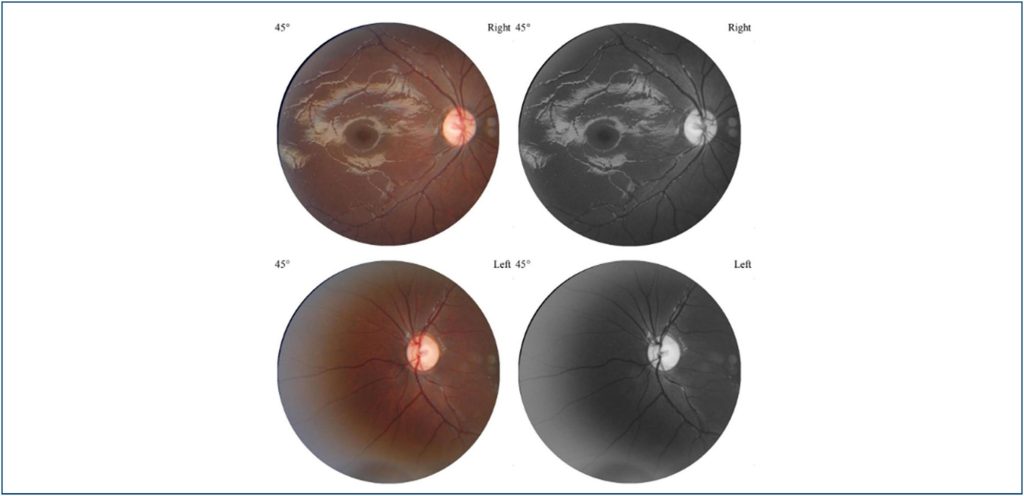

Achados oftalmológicos na síndrome de Lamb-Shaffer

A síndrome de Lamb-Shaffer é uma condição rara caracterizada por distúrbios do neurodesenvolvimento causados por haploinsuficiência do gene SOX5 no cromossomo 12p12. Clinicamente, manifesta-se com retardo do crescimento, atraso global do desenvolvimento neurológico, atraso na fala, características faciais dismórficas e anormalidades musculoesqueléticas, cardíacas e geniturinárias. Embora frequentes, as apresentações oftalmológicas dessa síndrome não estão bem consolidadas na literatura. Neste trabalho, objetiva-se relatar um novo caso dessa rara afecção, evidenciando os aspectos oftalmológicos de sua condição.